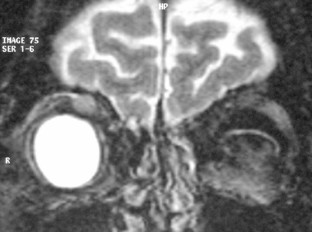

Eine 53-jährige Patientin stellte sich mit einer seit 18 Monaten bestehenden tastbaren Raumforderung der rechten medialen Orbita vor. Das linke Auge war im Kindesalter wegen einer perforierenden Verletzung enukleiert worden. Eine auswärts durchgeführte orbitale Biopsie hatte bis auf unspezifische Entzündungszeichen keine klärende Diagnose erbracht. Eine auswärts durchgeführte systemische Therapie mit Kortikosteroiden war ohne Erfolg. Eine zweite orbitale Biopsie wurde in unserer Klinik durchgeführt und zeigte einen solitären fibrösen Tumor (SFT) der Orbita. Eine mediale Orbitotomie mit Tumorexzision erfolgte und die histologische Untersuchung des exzidierten Tumors ergab einen SFT der Orbita mit fokaler sarkomatöser Transformation. Die Patientin stellte sich 3 Jahre später mit einer neuen Raumforderung in einer MRT-Kontrolluntersuchung vor. Bei hochgradigem Verdacht auf ein Rezidiv wurde eine Orbitotomie mit Exzision der Raumforderung durchgeführt. Die histologische Untersuchung zeigte einen rezidivierenden SFT der Orbita mit sarkomatöser Transformation in seiner gesamten Ausdehnung. Anschließend wurde eine Radiotherapie mit einer Gesamtdosis von 59,4 Gy durchgeführt. Die Patientin war tumorfrei bei der letzten Kontrolluntersuchung 3 Jahre später.

A 53-year-old female patient presented with a palpable mass in the right medial orbit which had been present for 18 months. The left eye had been enucleated in childhood due to a perforating injury. An orbital biopsy performed ex domo showed unspecific inflammatory tissue but no definite diagnosis was made and systemic therapy with corticosteroids was unsuccessful. A second orbital biopsy was performed in our clinic and revealed a solitary fibrous tumor (SFT) of the orbit. Medial orbitotomy with tumor excision followed and the histological examination of the excised tumor established the diagnosis of SFT of the orbit with focal sarcomatous transformation. The patient presented 3 years later with a new orbital mass in a control MRI examination. Relapse was suspected and orbitotomy with excision of the mass was performed. The histological examination revealed a relapse of the SFT with sarcomatous transformation in the whole extent of the tumor. Radiotherapy with a dosis of 59.4 Gy was subsequently performed. The patient remained tumor-free in the most recent control examination 3 years later.

Abb. 1